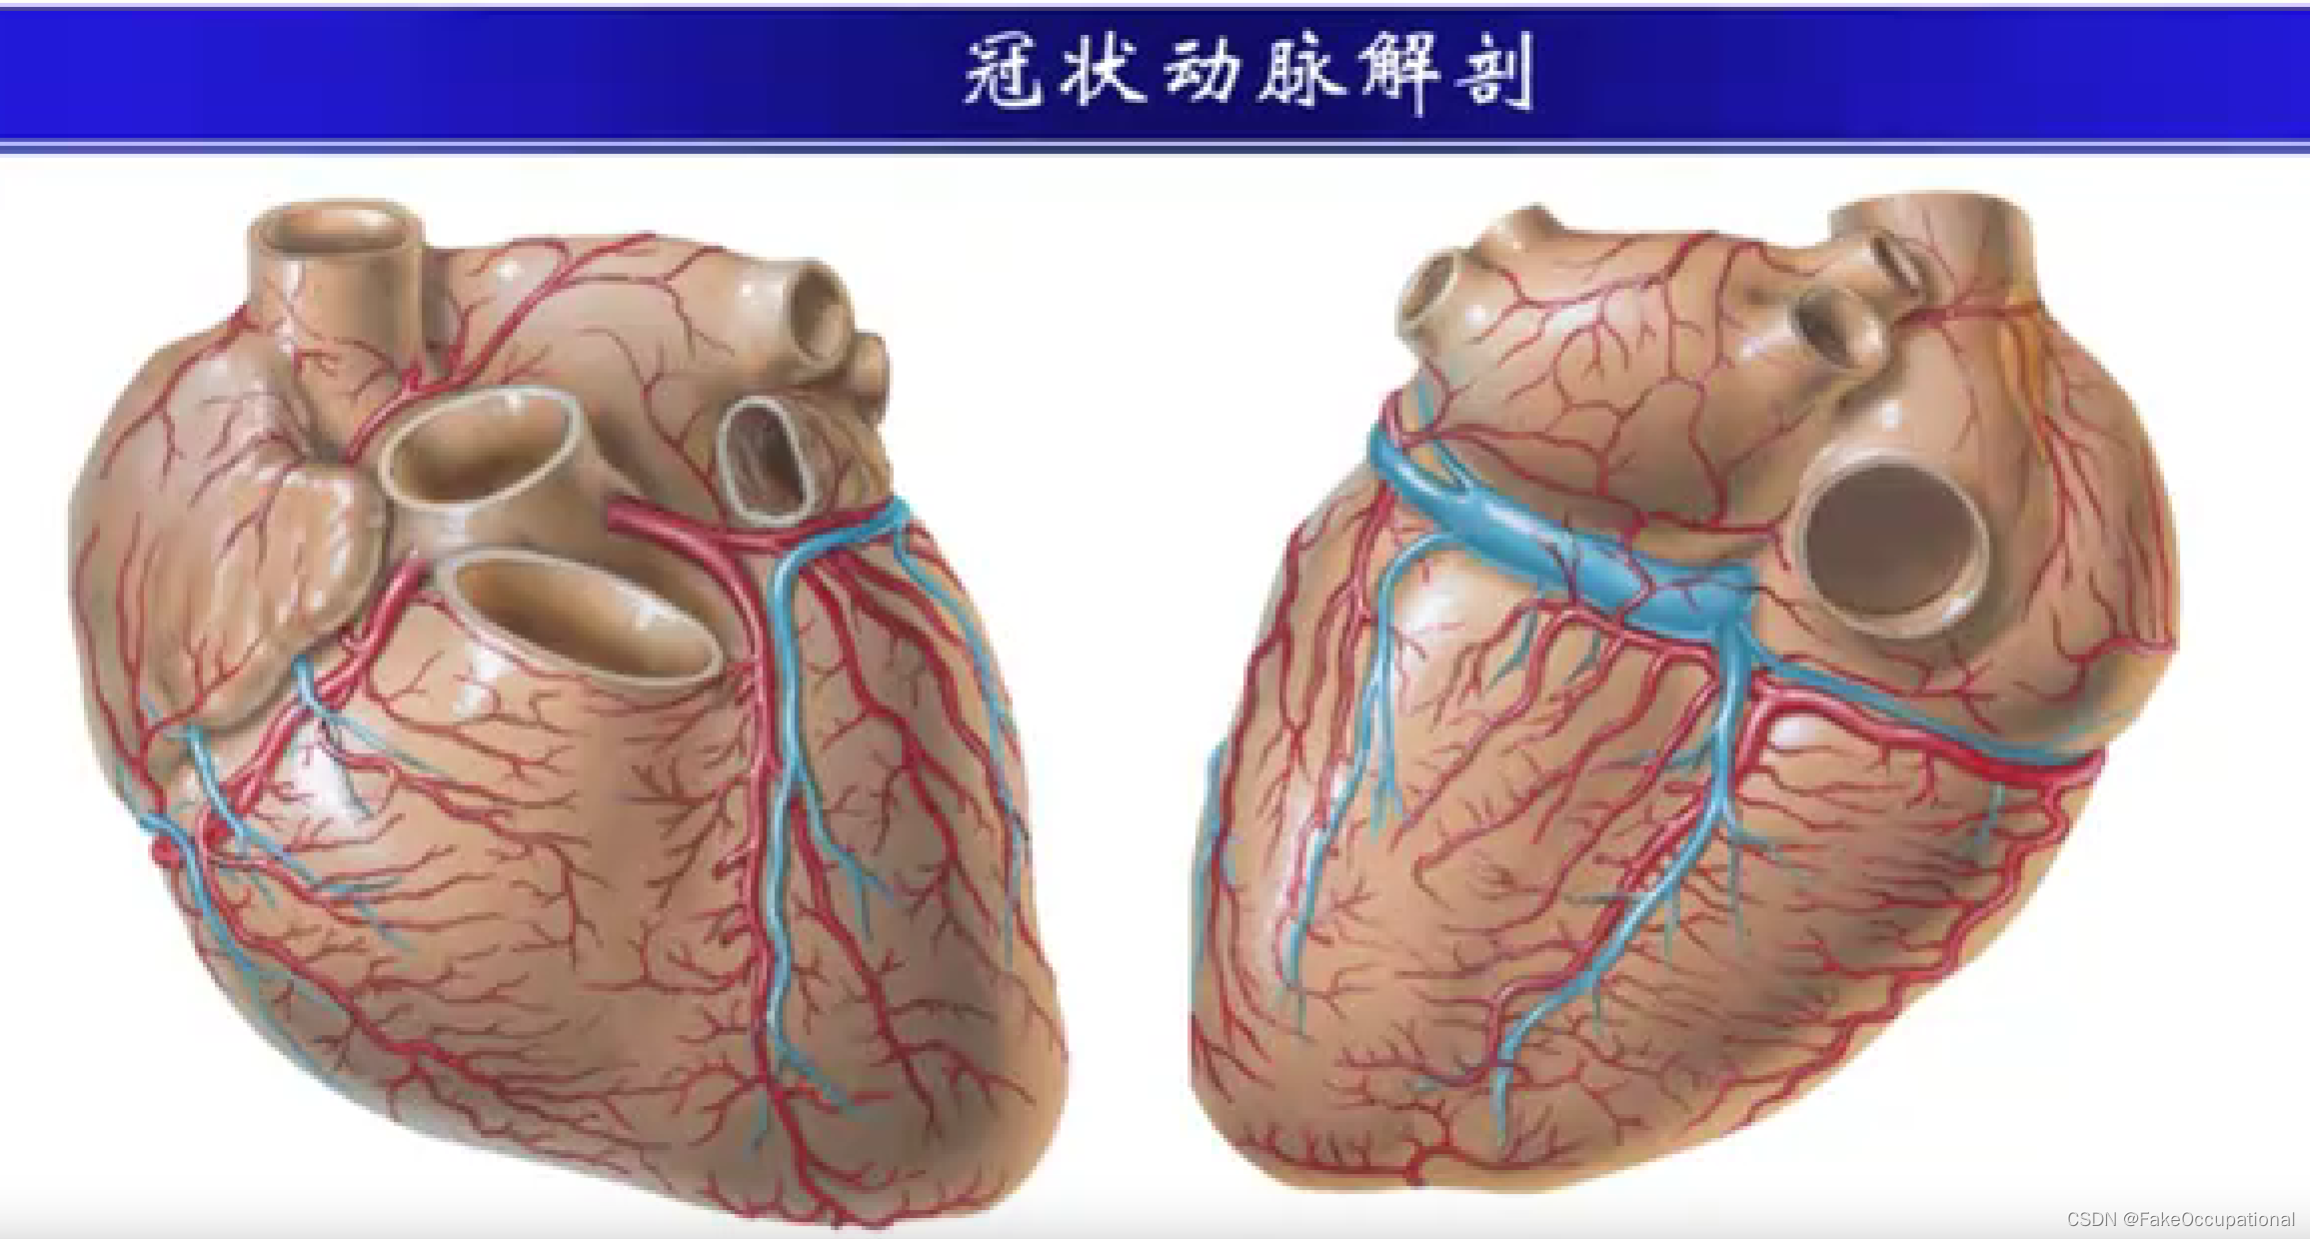

冠心病超声诊断

冠心病的诊断方法

- 心电图

- 心脏核素扫描

- 超声心动图

- 螺旋CT

- 心脏核磁共振

- PET-CT

- 冠状动脉造影 (金标准)